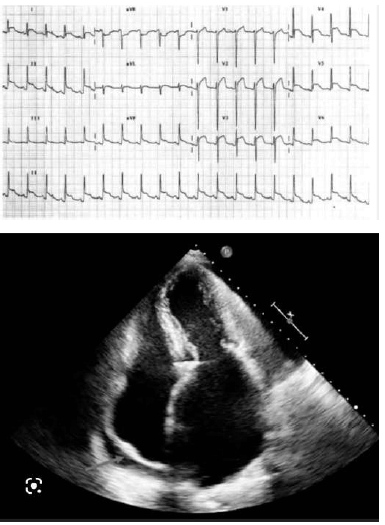

Um homem de 32 anos de idade, sem comorbidades, vem apresentando, há 6 dias, quadro de tosse seca, dor torácica que piora ao tossir e ao deitar, mialgia, palpitações, dispneia aos moderados esforços, afebril, estertores crepitantes em bases pulmonares. Apresenta pressão arterial de 92 x 48 mmHg, frequência cardíaca de 85 bpm, frequência respiratória de 22 ipm e saturação de oxigênio de 92% (ar ambiente). Realizou exames laboratoriais que evidenciaram os seguintes resultados: Hb = 14,5 g/dL; Ht = 43%; leucócitos = 6.500/mm3 (segmentados = 72%); linfócitos = 10%); plaquetas = 250.000/mm3; PCR = 4,5 mg/dL (VR < 1,0 mg/dL); DHL = 450 U/L (VR < 220 U/L); troponina = 45 ng/L (VR < 14 ng/L); creatinina = 1,1 mg/dL (VR < 1,2 mg/dL); ureia = 84 mg/dL (VR: 10 a 50 mg/dL); sódio = 138 mmol/L (VR = 135 a 145 mmol/L); potássio = 4,1 mmol/L (VR = 3,5 a 5,0 mmol/L). A tomografia de tórax revelou opacidades em vidro fosco acometendo 25% do parênquima pulmonar e discreto derrame pleural bilateral. A seguir, são apresentados os resultados do ECG e o ecocardiograma realizados.

Com base nas informações apresentadas nesse caso clínico, assinale a alternativa que indica a principal hipótese diagnóstica cardiológica do paciente.